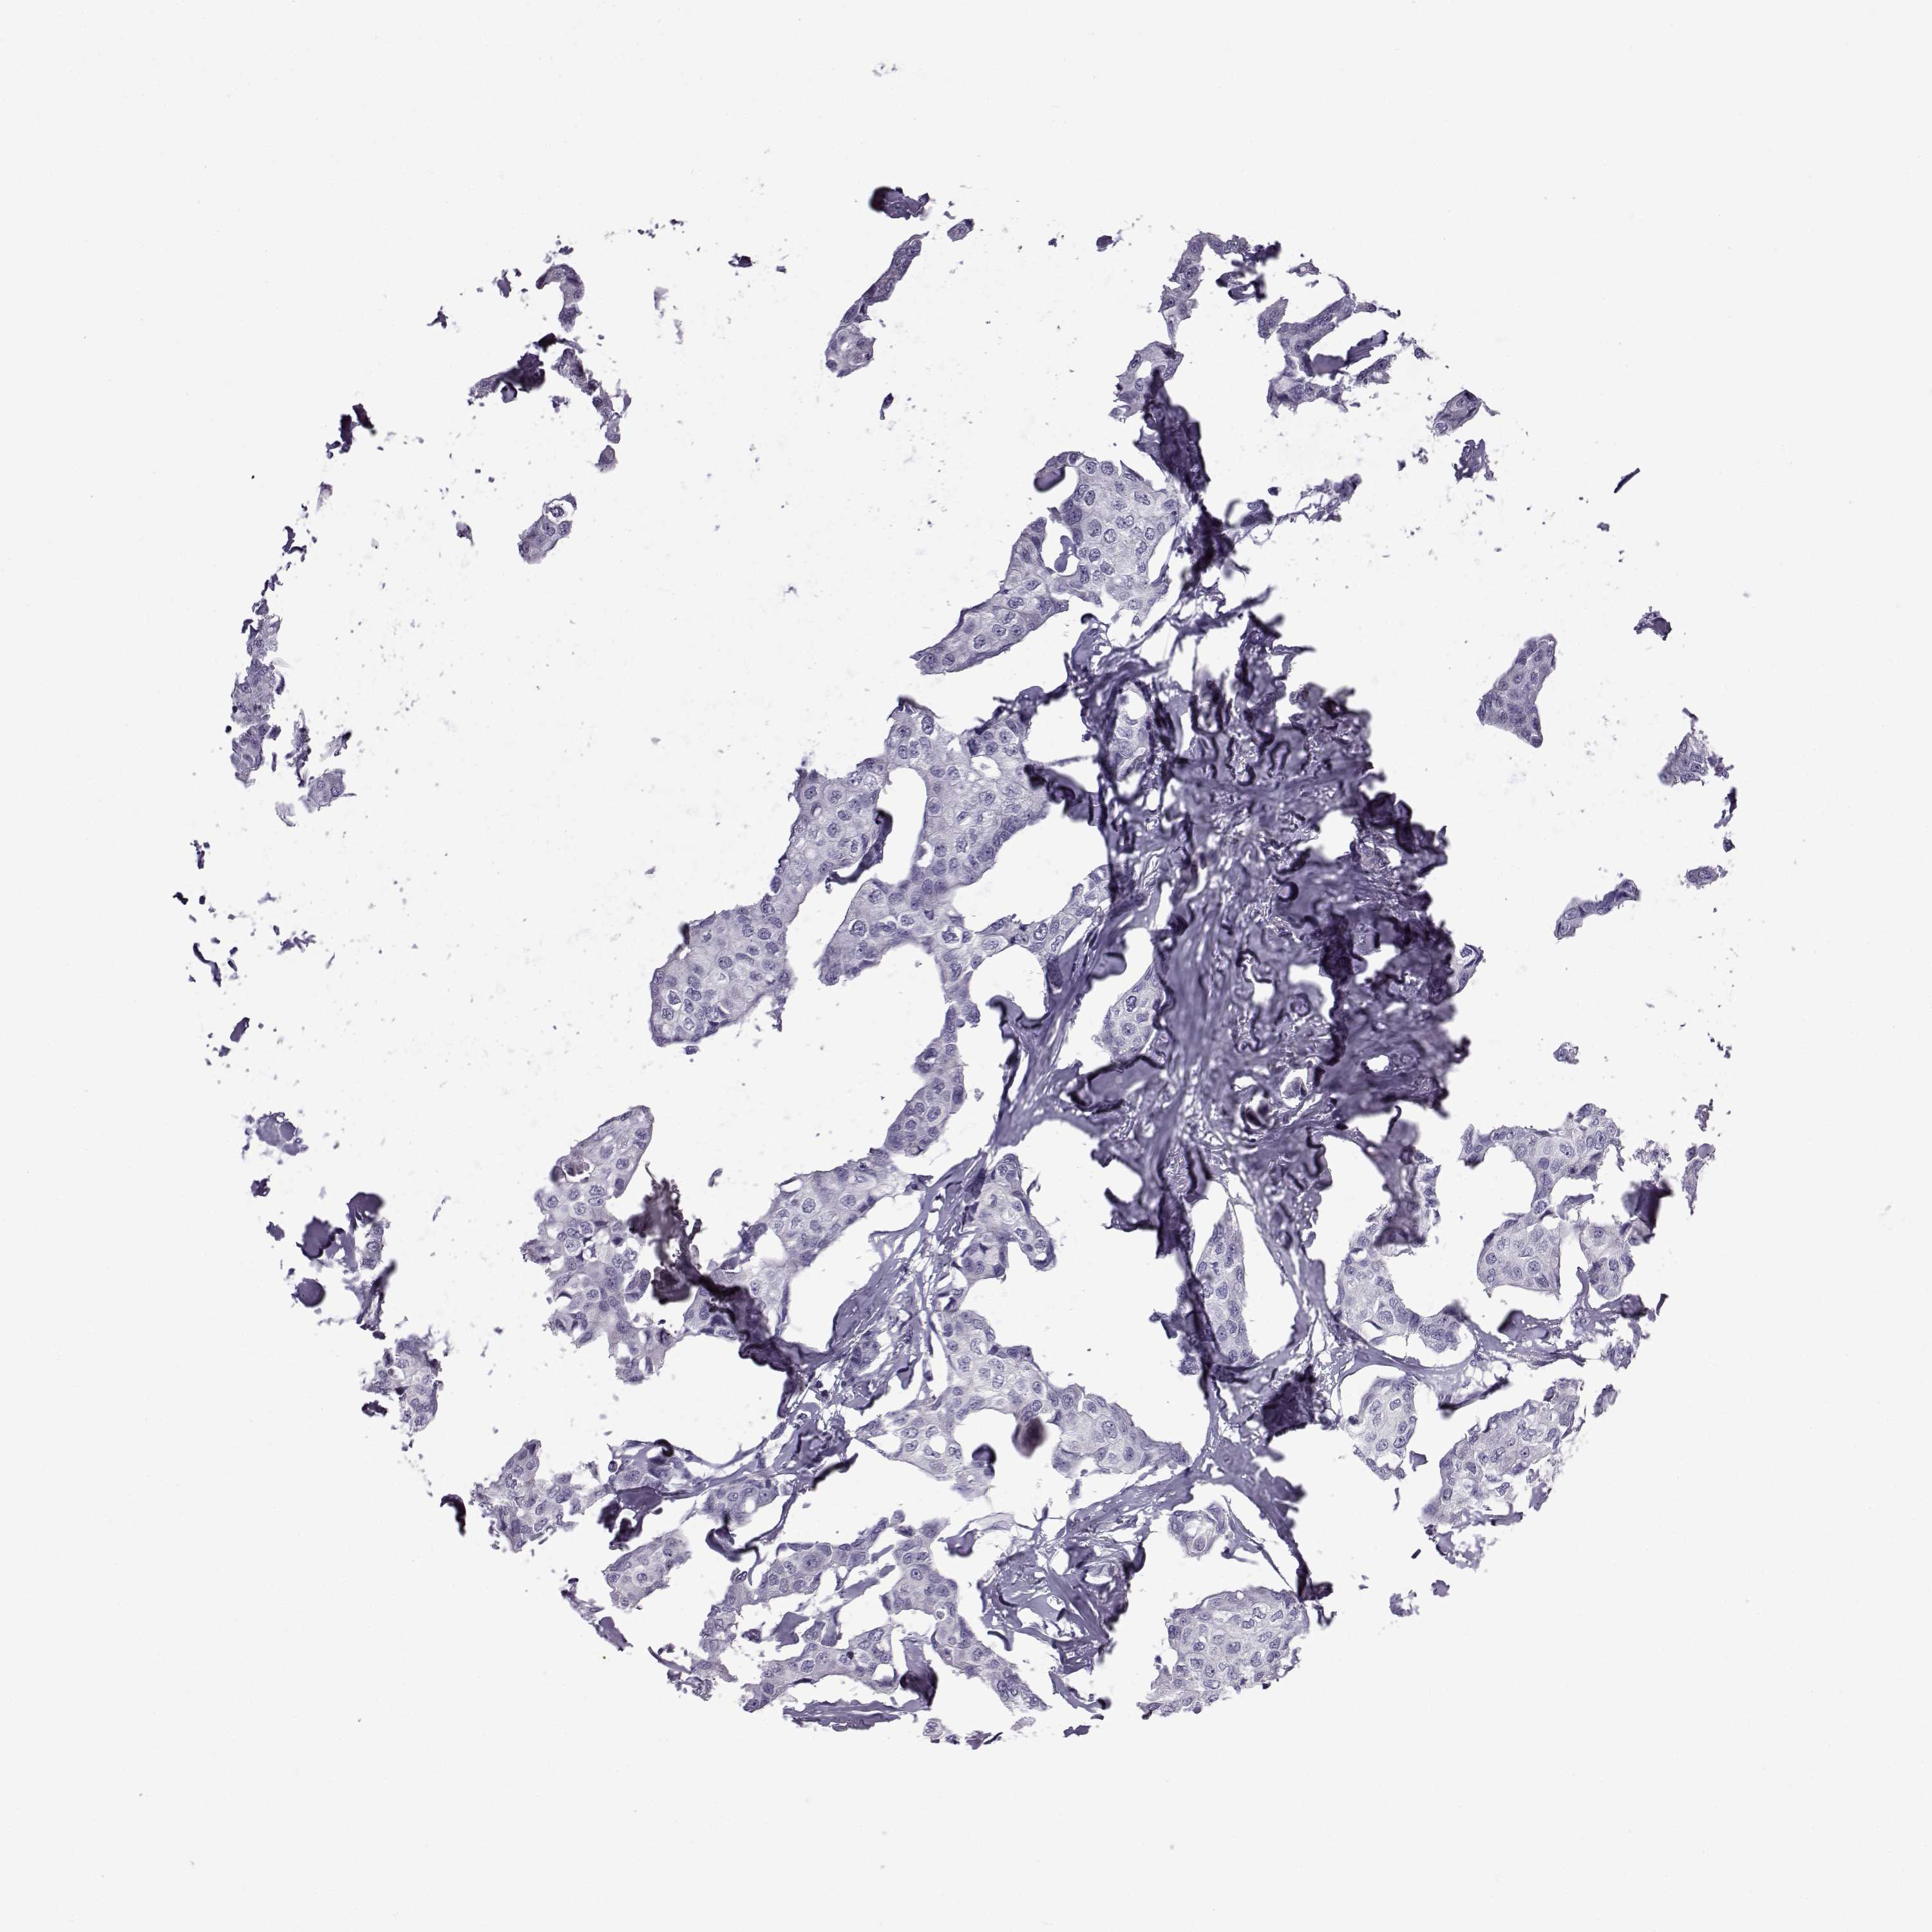

Breast cancer

Human cancer

Breast invasive carcinoma

OIP5 is not prognostic in Breast Invasive Carcinoma (TCGA)